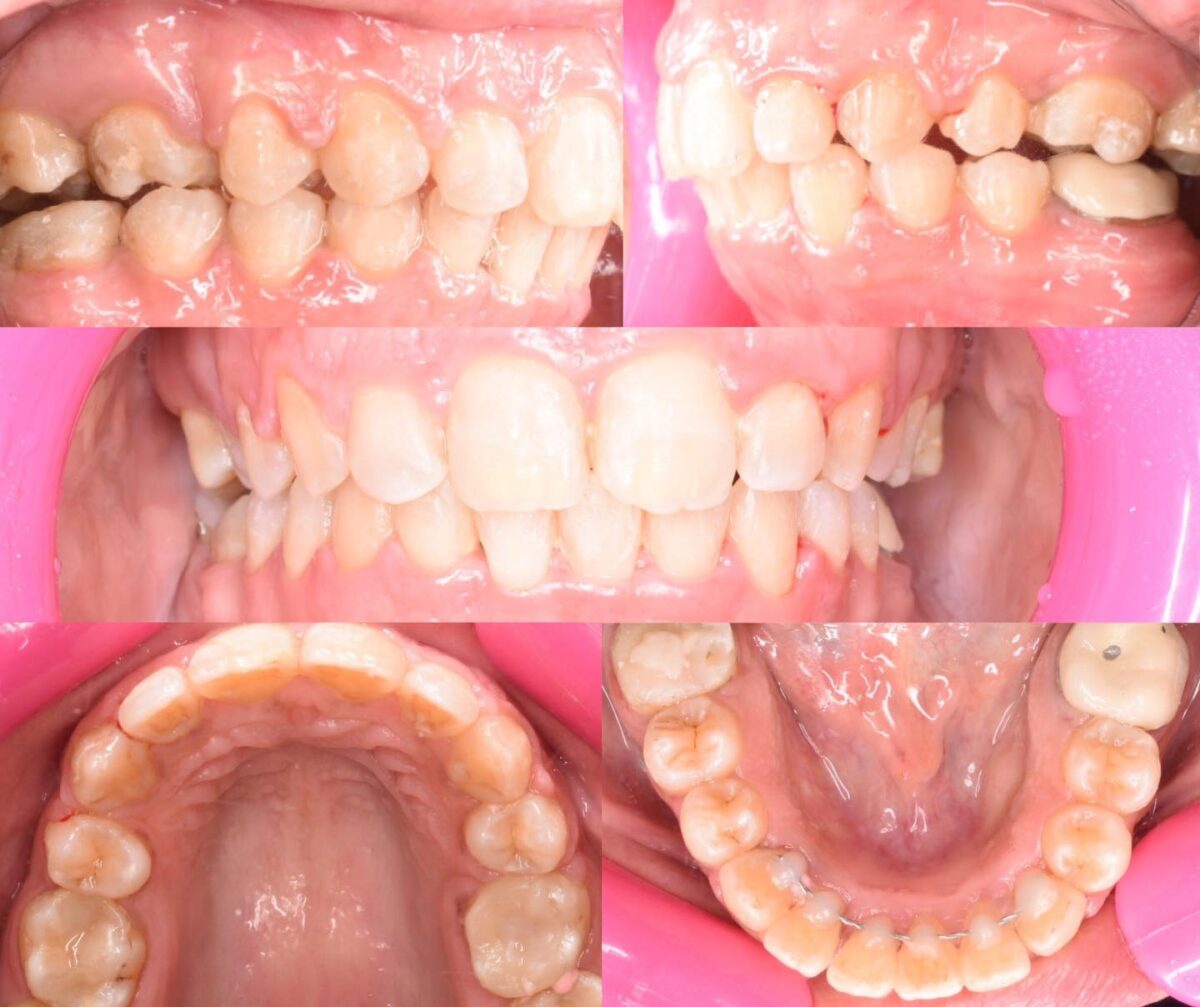

للي محتاجين تقويم، سواء معدني أو شفاف، العيادة بتوفر أحدث حلول التقويم المناسبة لكل حالة، مع متابعة دورية لضمان تقدم العلاج بالشكل المطلوب. وكمان لو في فقدان سن، بيتم تعويضه بزرعات أسنان من التيتانيوم المعتمد دوليًا بعد فحص شامل لعظام الفك وأشعة دقيقة، لضمان أفضل ثبات ونتيجة تدوم سنين.